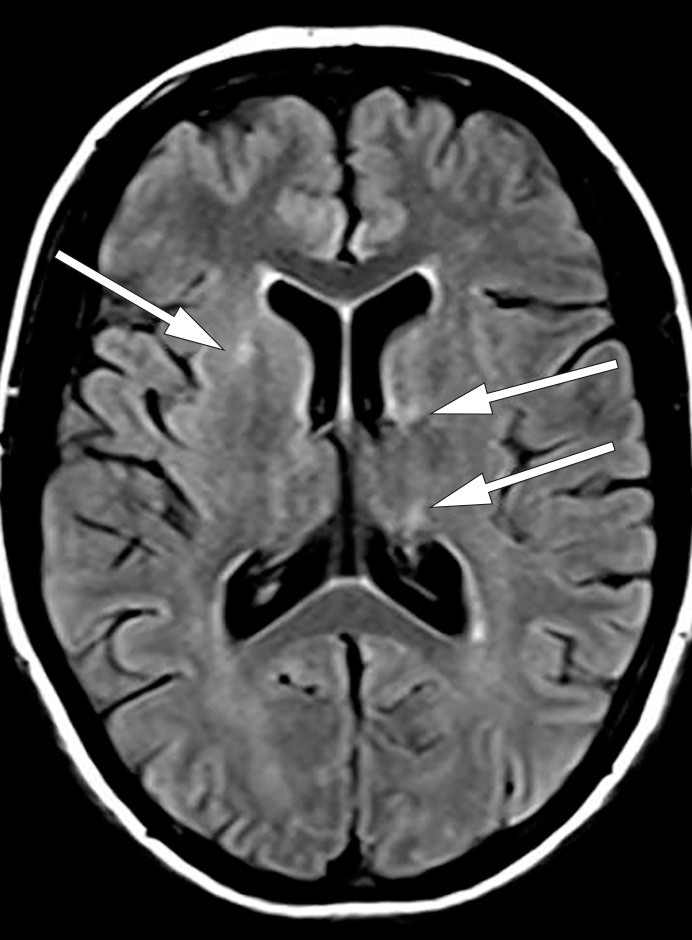

MR caput viste forandringer i mesencephalon, øvre del av pons og venstre cerebellarpedunkel, og i høyre hippocampus. Hjerneforandringene ble tolket som iskemiske lesjoner (fig 1). MR-angiografi var uten patologiske funn. Derimot var EEG patologisk, med intermitterende langsom thetaaktivitet frontotemporalt bilateralt. Enfotonstomografi (SPECT) viste nedsatt perfusjon i høyre cerebellarhemisfære og basalt temporalt på høyre side.

På bakgrunn av feber, forhøyet celletall i spinalvæsken og nevrologiske utfall hadde vi mistanke om uspesifikk viral eller bakteriell meningoencefalitt. Pasienten ble derfor behandlet både med antibiotika og antivirale midler, men behandlingen ble stoppet etter at mikrobiologiske prøver var negative. Dette inkluderte Borrelia-serologi både i serum og spinalvæske, noe som er ikke uvanlig etter vellykket behandling (2). Ved bakteriell meningoencefalitt er celletallet i spinalvæsken vanligvis sterkt forhøyet (gjerne over 1 000 hvite blodceller/mm³), glukoseratioen lav, og allmenntilstanden forverres raskt med feber og bevissthetsendring. Pasienten hadde imidlertid kun lett forhøyet celletall og normal glukoseratio. Bred utredning med tanke på autoimmun, inflammatorisk, infeksiøs og malign sykdom var uten positive resultater. Differensialdiagnostisk ble det vurdert om MR-funnet av iskemiske lesjoner kunne peke i retning av progressiv multifokal leukoencefalopati (PML), en demyeliniserende tilstand som oftest rammer immunsupprimerte pasienter grunnet reaktivering av JC-virus (3). Spinalvæskeundersøkelse hos vår pasient viste ikke funn av JC-virus, og derfor vurdert vi progressiv multifokal leukoencefalopati som lite sannsynlig. Tilstanden ble isteden oppfattet som et uveomeningealt syndrom. Dette er en inflammatorisk multisystemsykdom som affiserer øye, indre øre, hud og meninger (4).

I løpet av et par dager ble pasienten somnolent og fikk økende muskeltonus i alle fire ekstremiteter, økte reflekser og bilateral plantarinversjon. CRP steg til 130 mg/l (< 5 mg/l), leukocytter til 18 · 10⁶/l (4,5 · 10⁶/l) og SR til over 100 mm/h. Gjentatte spinalpunksjoner viste lett leukocytose (16 · 10⁶/l celler) og lett forhøyet totalprotein (0,66 mg/l). Isoelektrisk fokusering av spinalvæske var uten tegn til intratekal IgG-produksjon. EEG endret seg på seks dager fra nærmest normalt til svært patologisk, med generalisert høyspent, langsom theta- og deltaaktivitet samt hyppige, skarpe potensialer frontotemporalt med trifasisk utseende. MR caput viste progresjon av signalavvikene i mediale venstre temporallapp (amygdala, uncus og fremre hippocampus) i basalgangliene og subkortikalt i begge hemisfærer (fig 2a og b).

Signalforandringene i disse områdene var uten tegn til diffusjonsrestriksjon, noe som talte mot ferskt iskemisk infarkt. MR-bildene ga derimot mistanke om viral encefalitt eller limbisk encefalitt. Det var imidlertid ikke påvist affeksjon av insula, basale frontallapp og gyrus cinguli, som ofte er involvert ved limbiske encefalitter (6).